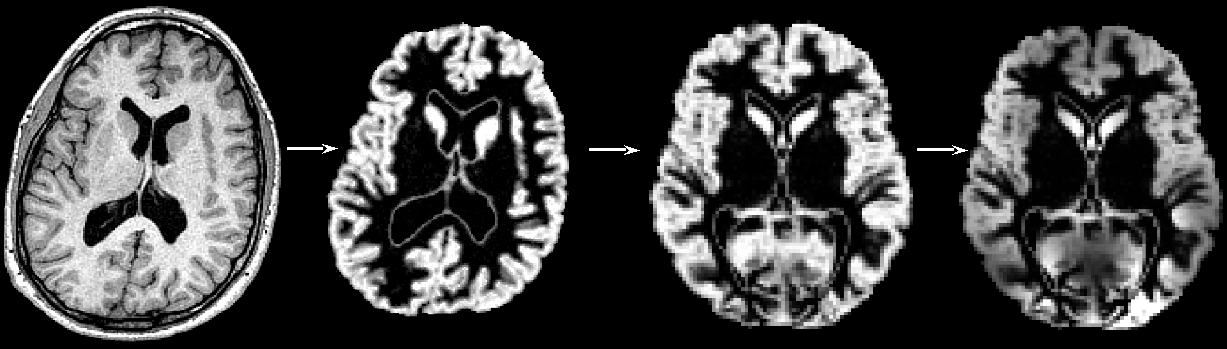

"Structural data was analysed with FSL-VBM (Douaud et al., 2007, https://fsl.fmrib.ox.ac.uk/fsl/docs/structural/fslvbm.html), an optimised VBM protocol (Good et al., 2001) carried out with FSL tools (Smith et al., 2004). First, structural images were brain-extracted and grey matter-segmented before being registered to the MNI 152 standard space using non-linear registration (Andersson et al., 2007). The resulting images were averaged and flipped along the x-axis to create a left-right symmetric, study-specific grey matter template. Second, all native grey matter images were non-linearly registered to this study-specific template and "modulated" to correct for local expansion (or contraction) due to the non-linear component of the spatial transformation. The modulated grey matter images were then smoothed with an isotropic Gaussian kernel with a sigma of ?? mm. Finally, voxelwise GLM was applied using permutation-based non-parametric testing, correcting for multiple comparisons across space."

First, all brain-extracted images are segmented into GM, WM and CSF. Then, GM images selected in the template_list file (*_struc_GM) are affine-registered to the GM ICBM-152 template, concatenated and averaged. This averaged image is then flipped along the x-axis and the two mirror images then re-averaged to obtain a first-pass, study-specific "affine" GM template (template_GM_init). Second, the template_list GM images are re-registered to this "affine" GM template using non-linear registration, concatenated into a 4D image called template_4D_GM, averaged, flipped along the x-axis. Both mirror images are then averaged to create the final symmetric, study-specific "non-linear" GM template at 2x2x2mm3 resolution in standard space.